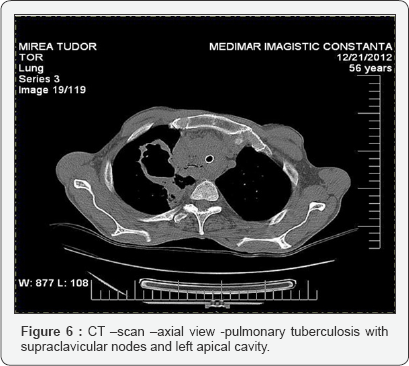

Percutaneous, CT scan guided needle biopsy of bone lesions for anatomo-pathologic studies is very important Biopsy from granulation resulted from surgical drainage of abscesses Microbiologic studies to confirm diagnosis and to isolate organisms for culture and susceptibility. Frequent negative Drainage Some cases of Pott disease are diagnosed following an open drainage procedure (eg, following presentation with acute neurologic deterioration) Figures 6 & 7.

Rx-of the thorax to evaluate for possible associated pulmonary findings:

• Cavity =advanced infection; with a high bacterial load

• Noncalcified round infiltrates==differential with lung carcinoma

• Calcified nodules (usually 5-20 mm): Tuberculomas= old infection

• Primary TB== pneumonia-like ==infiltrative process in middle or lower lung

• Reactivation TB: Pulmonary lesions in posterior segment of right upper lobe, apicoposterior segment of left upper lobe, and apical segments of lower lobes

• TB associated with HIV ==atypical lesions or normal chest radiographic findings

• Healed and latent TB: Dense nodules in hilar or upper lobes;

• Milliary TB: Numerous small, nodular lesions that filled both lungs ,septicemia

• Pleural TB empyema